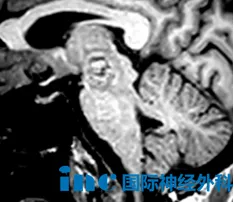

59岁周女士因右侧丘脑-中脑出血性病变,考虑海绵状血管畸形,临床表现为右眼不能睁开、视物重影、视野受限伴左侧肢体肌力下降。保守治疗后症状部分缓解,但遗留右眼上睑下垂、复视、视野受限及左侧肢体无力,病变仍存在再出血风险。面对脑干区手术的高风险性,周女士与家人一度焦虑犹豫。经多专家咨询后,他们获悉国际脑干手术专家巴特朗菲教授。巴教授详细分析影像资料后指出,病变位于中脑内侧被盖区动眼神经核核心区,侵犯第三脑室室管膜,再出血风险极高,手术指征明确。他强调:“预后通常良好。我已成功处理多例类似病变,并发表相关研究成果。若患者决定手术,全切是我们的目标。”